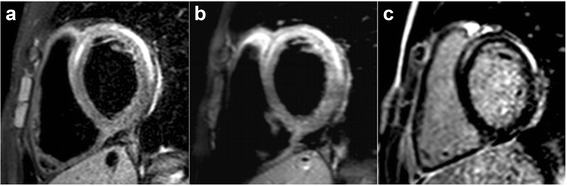

Results: For the 143 patients meeting inclusion criteria, the median age was 16.0 years (range, 0.1-20.3) and 139 (97 %) were hospitalized at the time of CMR. The median time from presentation to CMR was 2 days (0-28). The median left ventricular ejection fraction at CMR was 56 % (10-74), with 29 (20 %) below 45 %. The median right ventricular ejection fraction was 54 % (15-72), with 11 (8 %) below 40 %. There was significant variability among centers in the types of tissue characterization techniques employed (p < 0.001). Overall, late gadolinium enhancement (LGE) was used in 100 % of studies, followed by T2-weighted imaging (T2W) in 69 %, first-pass contrast perfusion (FPP) in 48 %, and early gadolinium enhancement (EGE) in 28 %. Abnormalities were most common with LGE (81 %), followed by T2W (74 %), EGE (55 %), and FPP (8 %). The CMR study was interpreted as positive for myocarditis in 117 patients (82 %), negative in 18 (13 %), and equivocal in 7 (5 %), yielding a sensitivity of 82 %. At a median follow-up of 7.1 months (0-87), all patients were alive and 5 had undergone cardiac transplantation. CMR parameters at presentation associated with persistent left ventricular dysfunction were larger left ventricular end-diastolic volume and lower left and right ventricular ejection fraction but not abnormal LGE.

Conclusions: Despite significant practice variation in imaging protocol among centers, CMR had a high sensitivity for the diagnosis of myocarditis in pediatric patients. Abnormalities were most often seen with LGE followed by T2W, EGE, and FPP. These findings should be useful in designing future prospective studies.